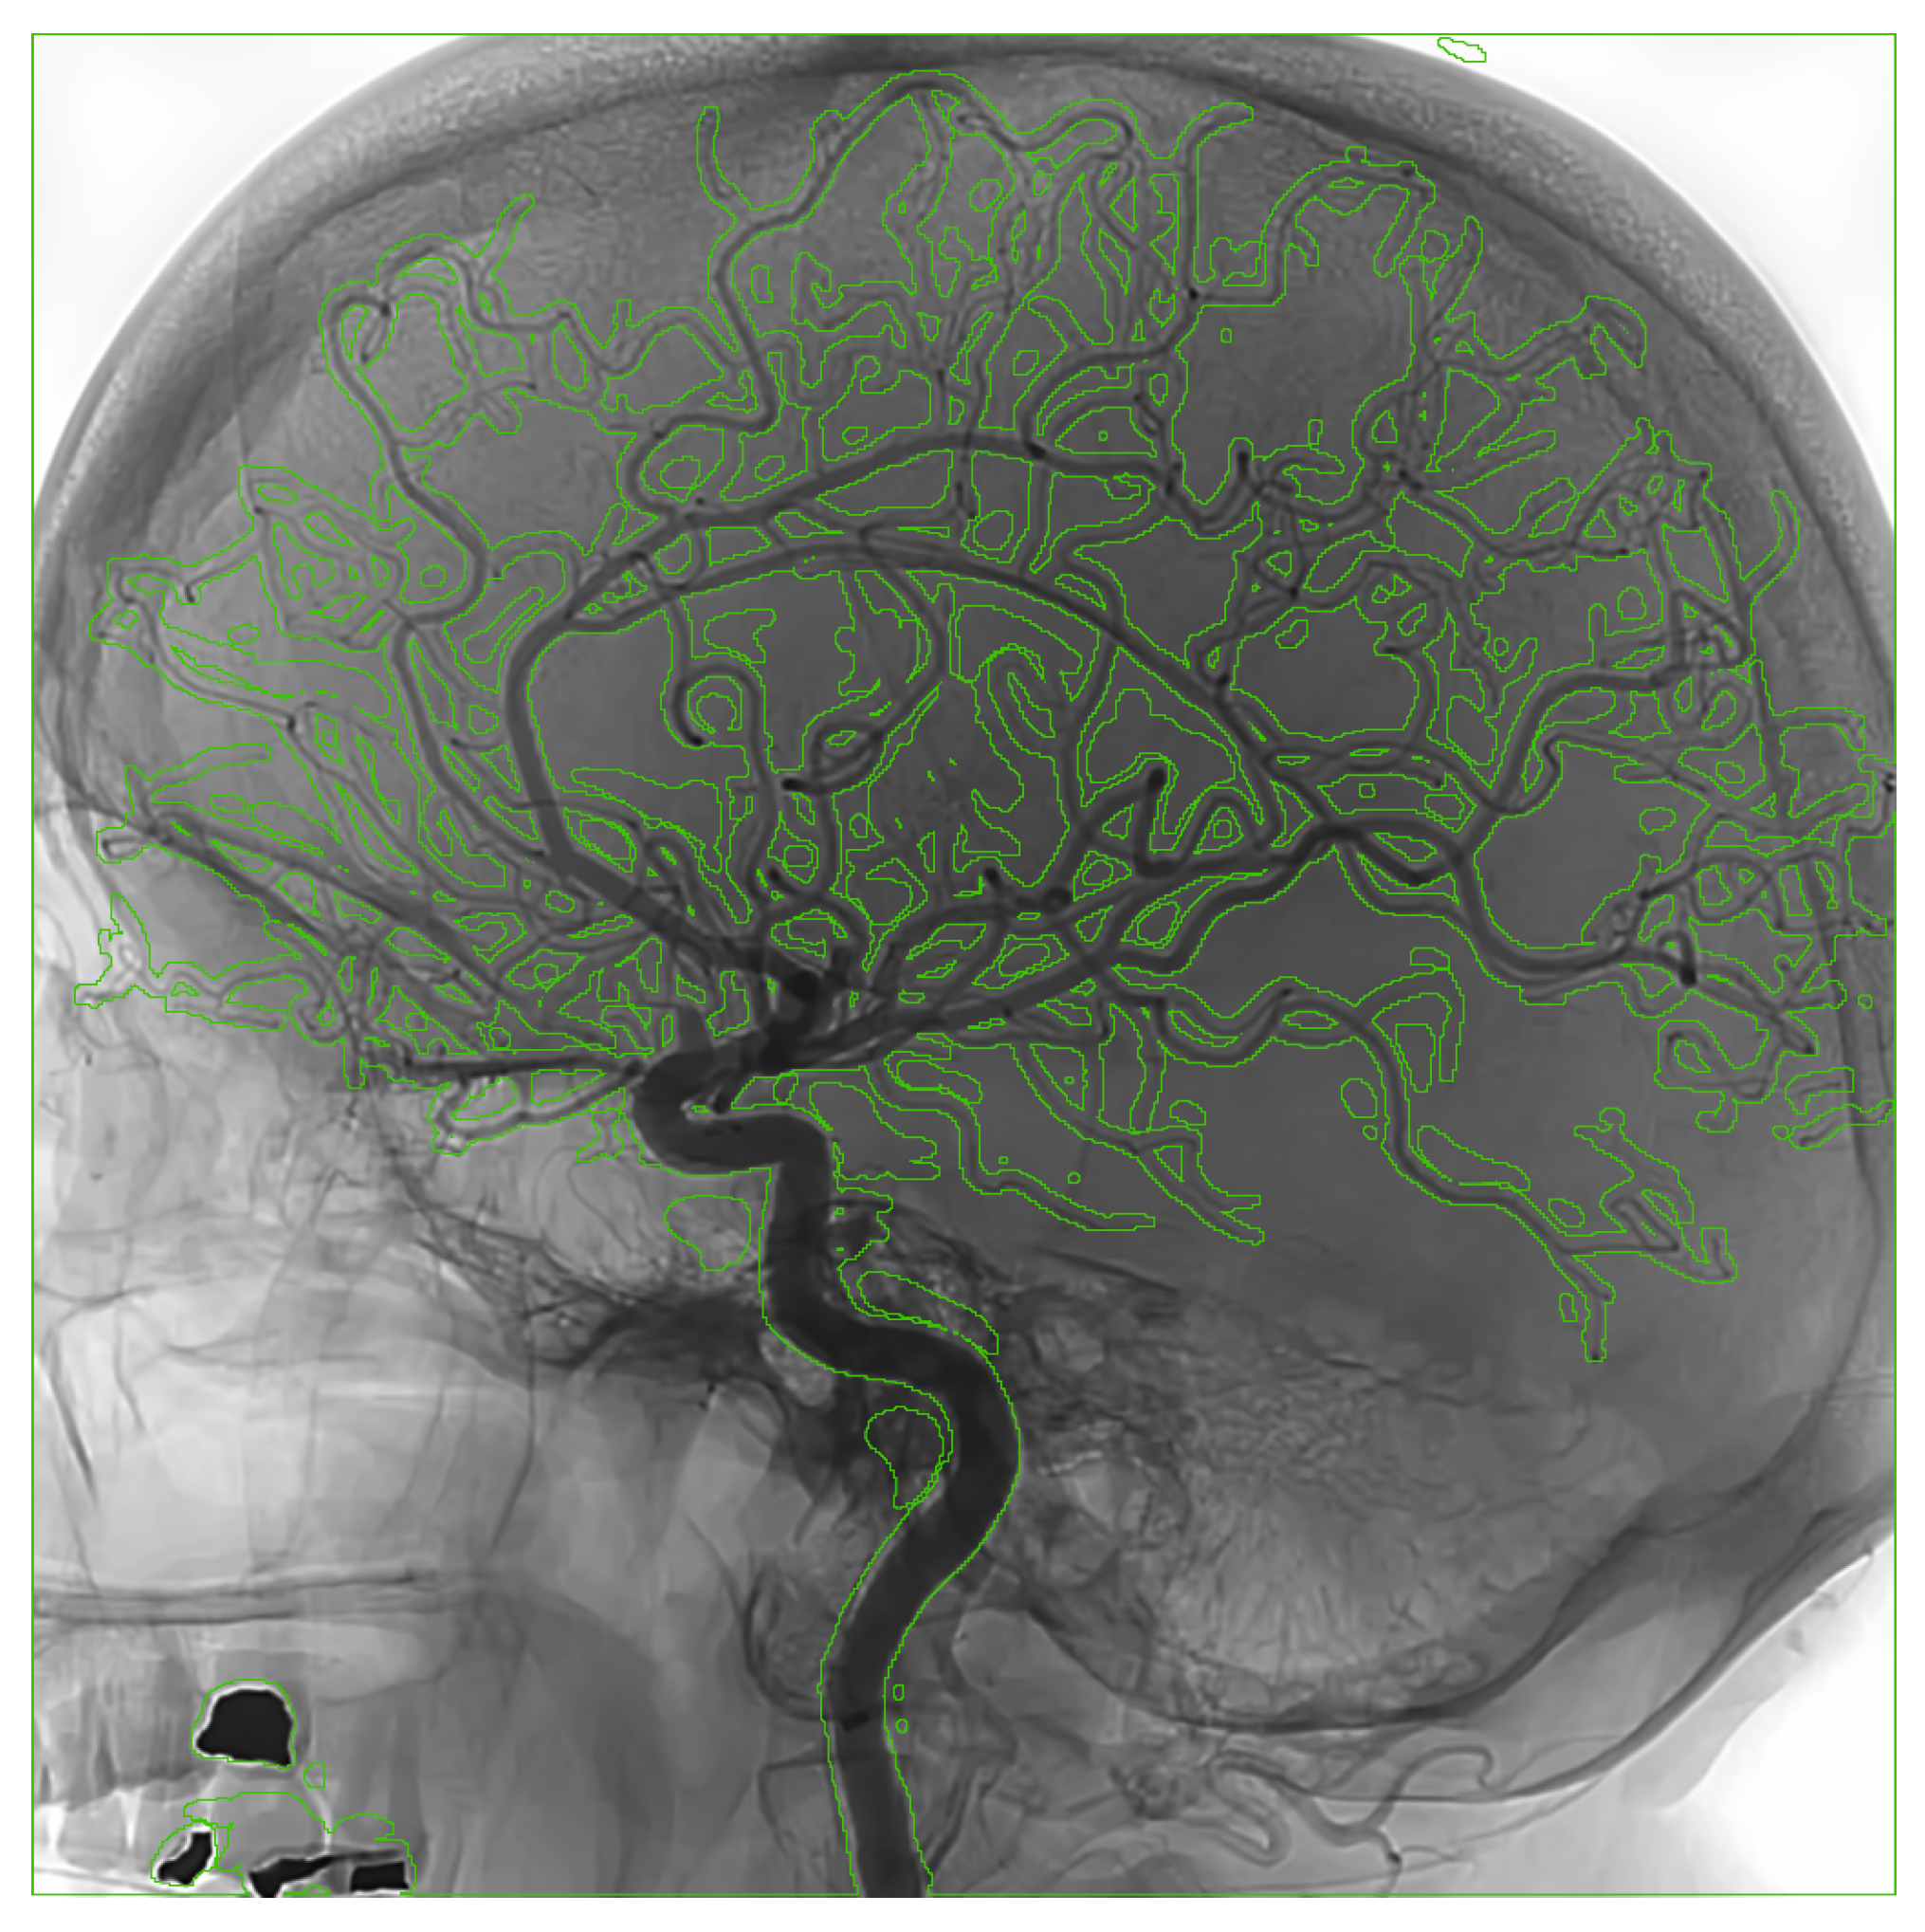

2.3.3. Dataset Description

The training and evaluation process utilized datasets from two individual patients (Figure 1), each comprising 122 angiographic images. For training the nnU-Net model, we used the first patient dataset with fully annotated images, which were manually segmented by our team. This dataset was split into training and validation subsets and served as the primary source for model development. In total, the full training dataset contained 273 images, including DSA images from publicly available datasets and images from the first patient. A separate portion of the data, fully processed and anonymized, was reserved as an independent test case to ensure unbiased performance evaluation.

Figure 1. Example angiographic frames from the two patient datasets used for nnU-Net training and evaluation.